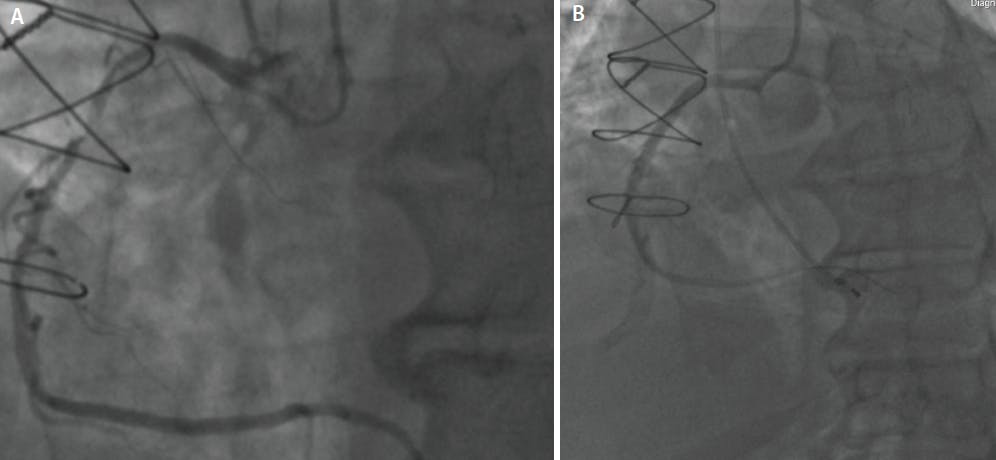

See Figures 1A and 1B as an example of a patient before and after low-contrast PCI. This patient had advanced stage 4 CKD and was referred for low-contrast PCI due to ongoing anginal symptoms refractory to optimal medical therapy, and we were able to complete the staged PCI with 5 mL of contrast.

Figure 1. Diagnostic imaging of the right coronary artery showing 85% to 90% tubular proximal/mid RCA lesion. Subsequent staged PCI given the patient’s advanced stage 4 CKD (A). Post-PCI image of the right coronary artery after one 3.5 X 38-mm drug-eluting stent was placed using IVUS and fractional flow reserve guidance. The entire PCI was completed with 5 mL of contrast (B).